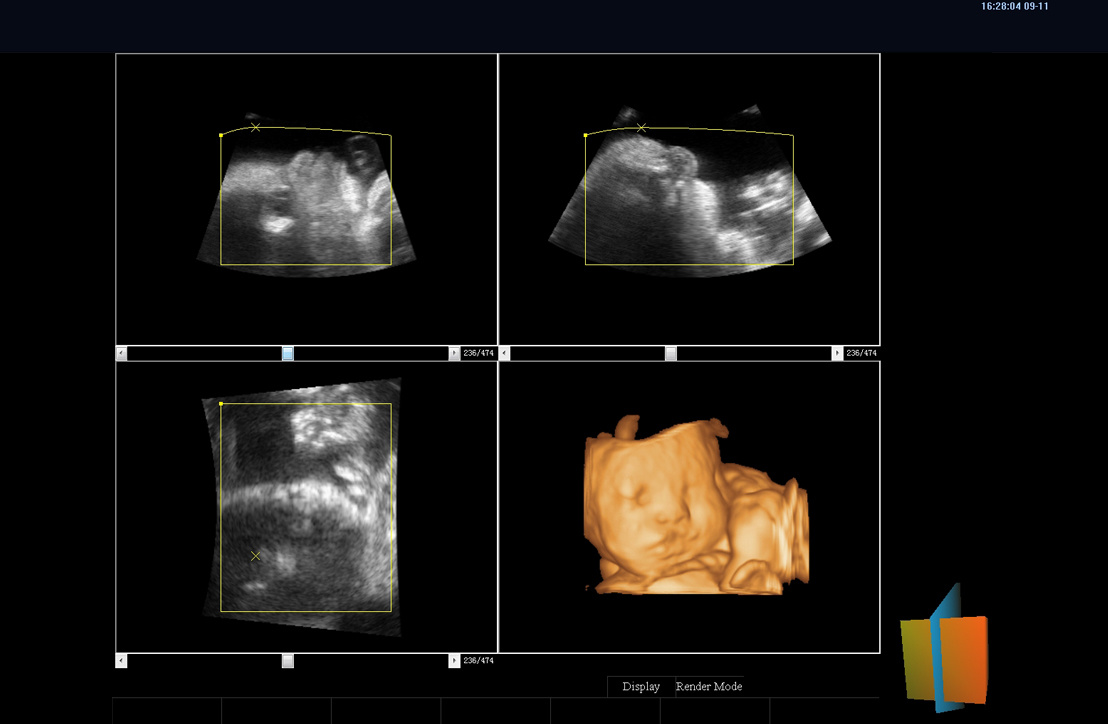

ViV65全面传承了uSeed高端技术平台,采用CPU+GPU多核并行处理技术,搭载高性能单晶体探头和复合晶体探头,可提供更宽带宽、更好穿透力和分辨力的超声影像,精准高效,全面提升临床诊断信心。

优异的临床图像